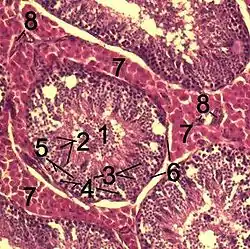

Histologische doorsnede door testisparenchym van een wild zwijn.

1. lumen van tubuli semeniferis

2.spermatiden

3. spermatocyten

4. spermatogonia

5. Sertolicel

6. myofibroblasten

7. Leydigcellen

8. haarvaten